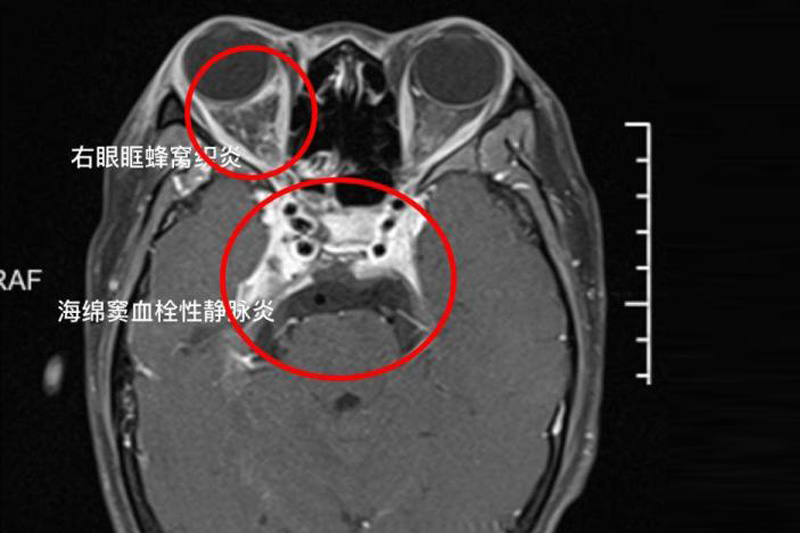

經診斷後,小楊證實患「海綿竇血栓性靜脈炎」,一種嚴重顱內感染,當時的她已右眼外凸、眼球沒法轉動等,醫生指若無及時治療,有可能導致死亡。幸而,她接受抗感染治療後,病情逐漸穩定。